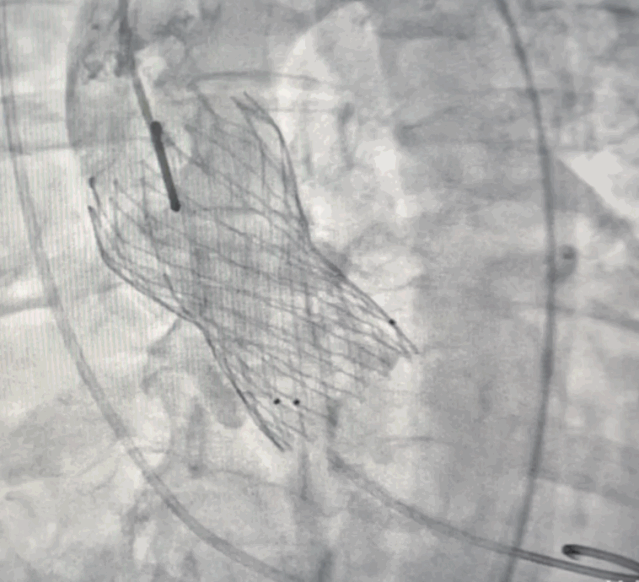

TAVI,指经导管的主动脉瓣置换,不开胸或胸部小切口的辅助下,逆行或顺行将处理好的瓣膜输送至主动脉根部,在不处理原瓣膜的情况下进行主动脉瓣置换。手术操作时间短,是当今国际上最先进的外科技术之一,对于高危的患者,是更为合适的治疗策略。

TAVI术中利用放射线置入瓣膜